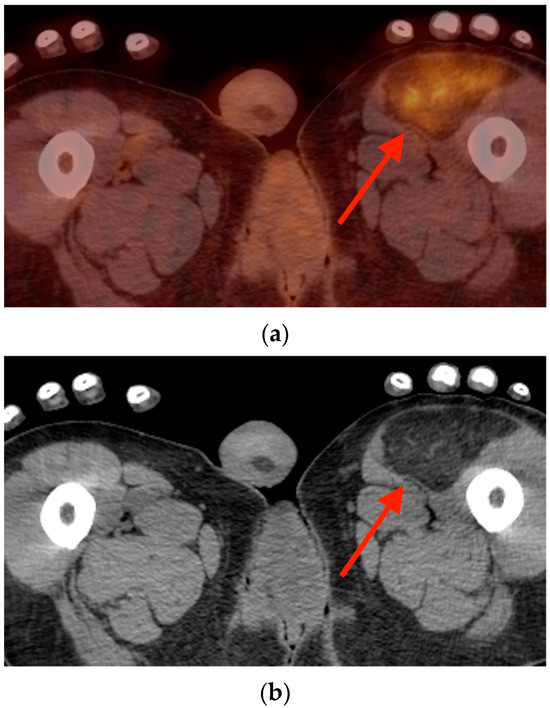

5.3. Hibernoma

6. Conclusions